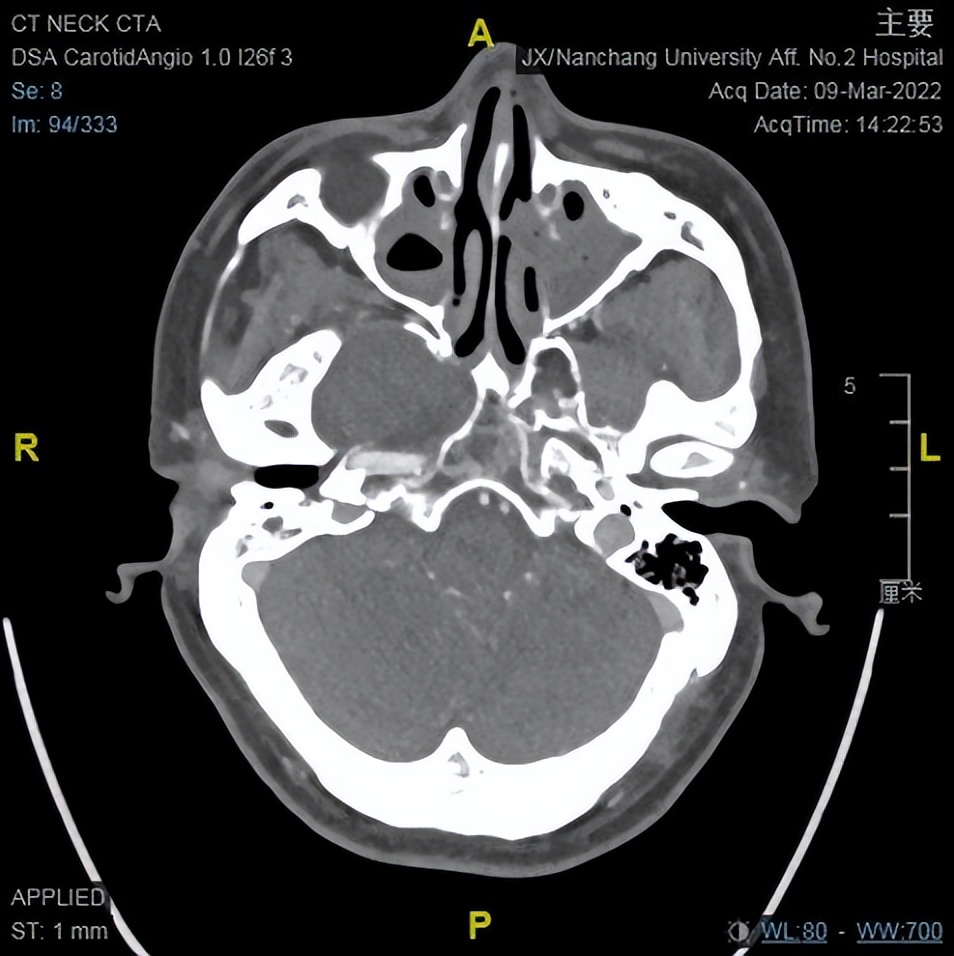

颈部至颅底CTA

中颅窝右侧鞍旁可见无强化稍低密度影,边缘可见少许钙化影,边界清晰,邻近骨质受压变薄,邻近颈内动脉受压内移